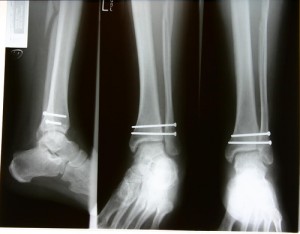

If it is two o’clock in the morning and you’re drunk, please take this advice: Don’t do it. No, I don’t need to know what “it” is. Don’t send that email to your boss/mother/romantic partner. Don’t go skinny dipping. Don’t click that ebay bid. And don’t try to remove those ankle screws. Sadly, I write too late for one young man. This patient had, at twenty-two, gotten drunk and went out and injured his leg (seeing a pattern here?). His ankle was fixed together with six screws and a metal plate. Over time, he found that these objects caused him pain, and was put on a waiting list to get them removed. One night, he decided that the waiting list could go to hell, took five shots, and started boiling some water like an old-timey pioneer whose wife was in childbirth. He sterilized a pocket knife, an allen key – which is basically one of those ikea screw drivers – and needles, and then sliced his own ankle open, using the scar from his last surgery as a guide. He removed five of the six screws, but was not able to get to the last of them. Begrudgingly he decided that the waiting list would have to do, and stitched himself up again.